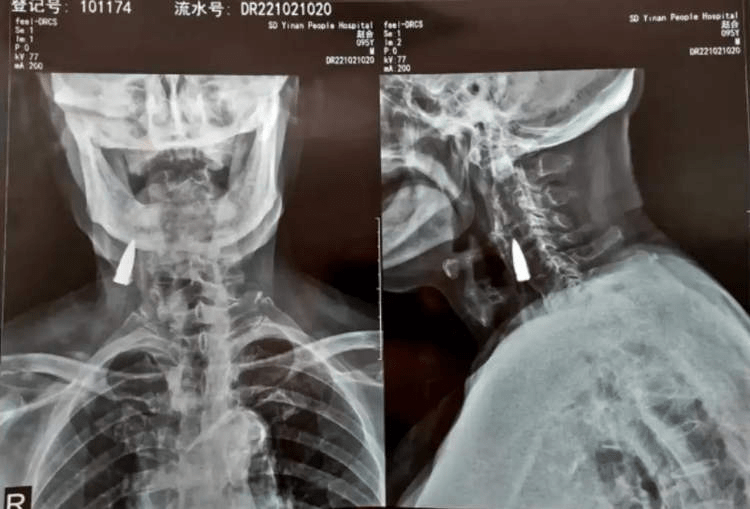

赵某在中国山东从自家阳台上摔了下来,直到他开始感到脖子有点不舒服,才真正出现了严重的症状。儿子看到了,就带他去医院请医生检查。当医生得知他摔倒的情况后,他们建议做x光检查,以排除摔倒造成的严重损害。出乎他们意料的是,他们在他的脖子上发现了一颗旧子弹!

在检查了x光片后,医生告诉赵贺和他的家人,子弹靠近一些主要血管,因为它不会造成问题,他们建议把它留下。